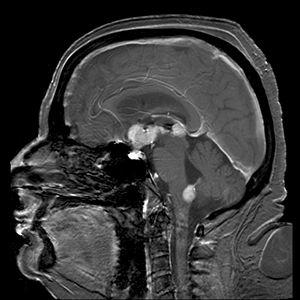

Brain magnetic resonance imaging showing primary central nervous system B-cell non-Hodgkin lymphoma of the sella turcica and hypothalamus, continuing to the tectum (intensely white areas in the middle). | |